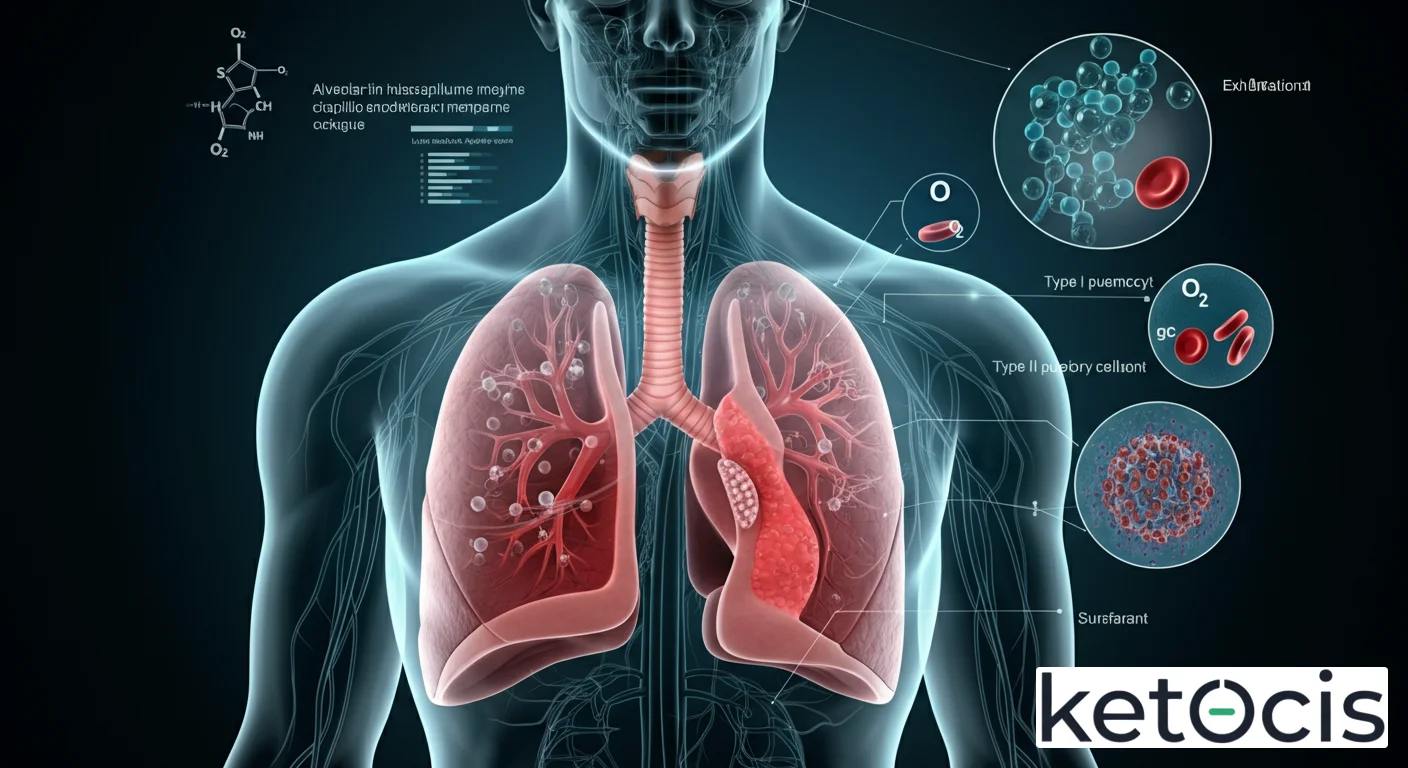

Anatomía Microscópica: La Arquitectura de la Vida

El sistema respiratorio humano es una obra maestra de la evolución, diseñada para maximizar la eficiencia del intercambio gaseoso. Tras un viaje a través de la tráquea, los bronquios y los bronquiolos, el aire finalmente llega a los sacos alveolares. Estos sacos son, en esencia, racimos de pequeños alvéolos individuales, cada uno con una pared extremadamente delgada que facilita la difusión de gases.

Ubicación y Estructura Macro-Microscópica

Los sacos alveolares se encuentran profundamente dentro del parénquima pulmonar, constituyendo la mayor parte del volumen del pulmón. Cada pulmón humano contiene millones de alvéolos (aproximadamente 300 a 500 millones), lo que confiere una superficie total de intercambio gaseoso asombrosamente grande, comparable a la de una cancha de tenis. Esta vasta superficie es fundamental para satisfacer las demandas metabólicas del organismo.

La pared de cada alvéolo es una maravilla de delgadez y eficiencia. Está compuesta principalmente por dos tipos de células epiteliales conocidas como neumocitos:

- Neumocitos Tipo I: Son células planas y muy delgadas que cubren el 90-95% de la superficie alveolar. Su principal función es proporcionar una barrera mínima para la difusión de gases, permitiendo un paso rápido y eficiente del oxígeno al torrente sanguíneo y del dióxido de carbono hacia el alvéolo.

- Neumocitos Tipo II: Aunque menos numerosos, estas células cúbicas son vitales. Son responsables de la producción y secreción del surfactante pulmonar, una mezcla compleja de lípidos y proteínas. El surfactante reduce la tensión superficial en el interior de los alvéolos, evitando que colapsen durante la espiración y facilitando la expansión pulmonar. Sin él, la respiración sería un proceso mucho más arduo y menos eficiente.

Además de los neumocitos, el tejido alveolar también alberga macrófagos alveolares, células inmunitarias que actúan como la primera línea de defensa contra partículas inhaladas, patógenos y desechos. Estos “guardianes” fagocitan sustancias extrañas, manteniendo la esterilidad y la limpieza del delicado ambiente alveolar.

La Membrana Alveolo-Capilar: El Punto de Contacto Vital

La verdadera magia del intercambio gaseoso ocurre en la membrana alveolo-capilar, también conocida como barrera hematogaseosa. Esta membrana es extraordinariamente fina, a menudo de solo 0.2 a 0.6 micrómetros de grosor, y está formada por la pared delgada del alvéolo, la membrana basal fusionada del alvéolo y el capilar, y la pared delgada del capilar sanguíneo. Es a través de esta barrera donde el oxígeno difunde desde el aire alveolar hacia la sangre en los capilares pulmonares, y el dióxido de carbono difunde desde la sangre hacia el aire alveolar para ser exhalado.